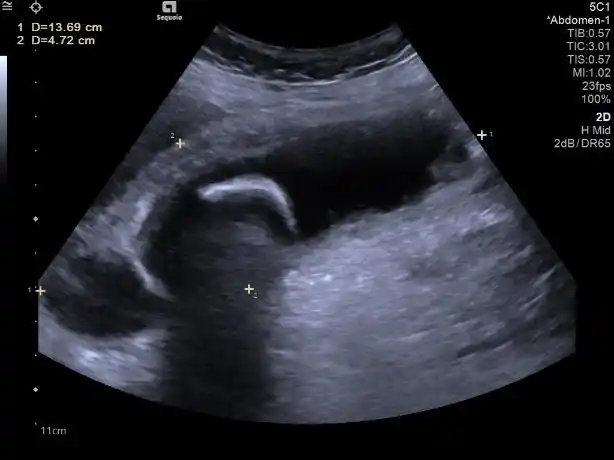

立竿见影精准排雷高危老年胆囊炎患者救治介入超声解难题